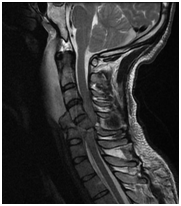

Anatómiai nyaki gerinc, láthatóvá MRI.

MRI lehetővé teszi, hogy megjelenítsék morfológiai változások: a csigolyatestek, porckorongok, gerincvelő, dura térben, az ideg gyökerek környező paravertebralis lágyrész, érrendszeri szerkezetek, amelyek a kutatási területen.

A módszertan az eljárás, mágneses rezonancia képalkotás a nyaki gerinc.

Mr képet spondylosis, extrudált lemez C3-C4, C4-C5, C5-C6, C6-C7.